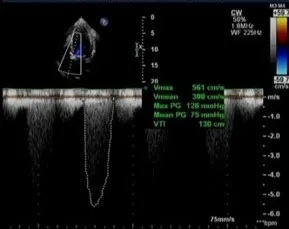

超声心动图:主动脉瓣环内径20mm,瓣口峰值流速5.6m/s,主动脉瓣峰值跨瓣压差126mmHg,平均跨瓣压差75mmHg,开放受限,关闭欠佳;主动脉瓣反流,彩束面积4.3cm2。

TAVR术后床旁超声描述:主动脉瓣位生物瓣位置、形态、回声、活动正常,生物瓣功能良好,主动脉瓣峰值跨瓣压差从术前126mmHg降至7mmHg,平均跨瓣压差从术前75mmHg降至3mmHg。心功能明显改善,LVEF恢复至73%,左室壁运动正常。